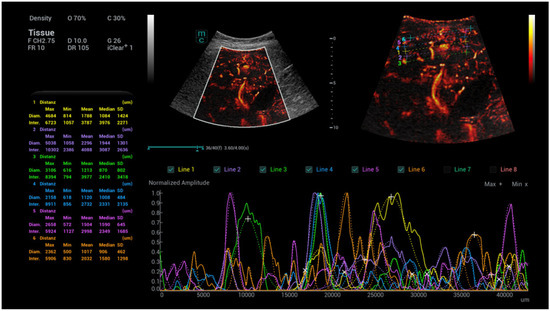

- Kaiser, U.; Vehling-Kaiser, U.; Kück, F.; Gilanschah, M.; Jung, F.; Jung, E.M. Super-Resolution contrast-enhanced ultrasound examination down to the microvasculature enables quantitative analysis of liver lesions: First Results. Life 2025, 15, 991. [Google Scholar] [CrossRef]